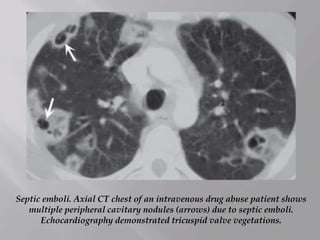

Septic emboli. Axial CT chest of an intravenous drug abuse patient shows

multiple peripheral cavitary nodules (arrows) due to septic emboli.

Echocardiography demonstrated tricuspid valve vegetations.